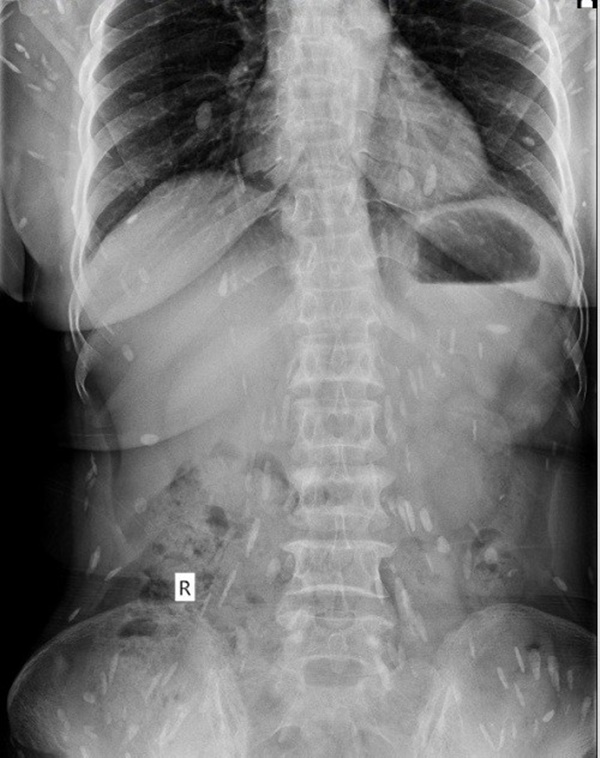

Hình ảnh sán lá gan lớn khắp cơ thể bệnh nhân Đ. - Ảnh: Bệnh viện cung cấp

Theo bà Đ, thời gian gần đây bà thường xuyên bị mệt mỏi, đầy bụng, đau đầu, đau ở vùng ngực và thắt lưng nên mua thuốc về tự điều trị nhưng bệnh tình không giảm. Lo lắng, ngày 19-3, gia đình đưa bà đến Bệnh viện Quốc tế Vinh thăm khám. Qua thăm khám, xét nghiệm, siêu âm, chụp X-quang, các bác sĩ kết luận bệnh nhân bị mắc bệnh sán lá gan sinh sống trong cơ thể đã nhiều năm, đang sinh sôi, lan ra trong nhiều bộ phận cơ thể.